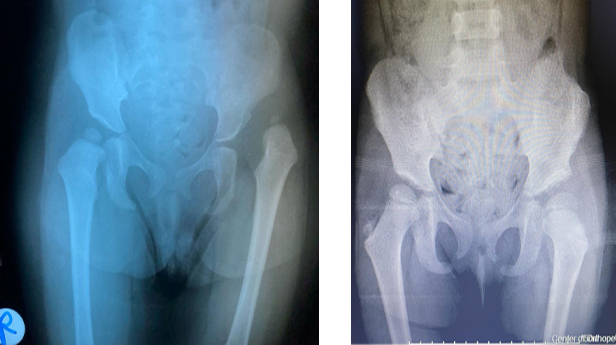

خلل التنسُّج الوركي ما بين الأطفال والمراهقين

يمكن لطبيب الأطفال اكتشاف مرض خلل التنسُّج الوركي، أو تشخيصه بتصوير الألتراساوند (تصوير فوق صوتي)، وذلك في حالة ولادة الطفل بالوضع المقعدي. ويتولى فريقنا علاج الأطفال المصابين بهذا الخلل بالوسائل غير الجراحية، إلى جانب الإجراءات الجراحية إذا لزم الأمر.

خلع الاطفال